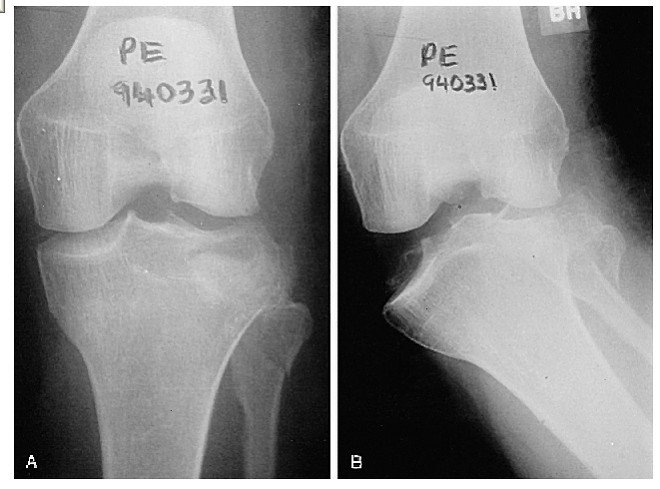

These fractures can be quite subtle and should always be considered when assessing acute knee injuries. Usually the common patterns of tibial plateau fractures are identified on plain films (AP, LAT, OBLIQUES).

This film shows a lateral tibial plateau fracture with depression and comminution.

There is a less obvious extension of the fracture through the medial tibial plateau and in fact the knee is no longer connected to the shin!